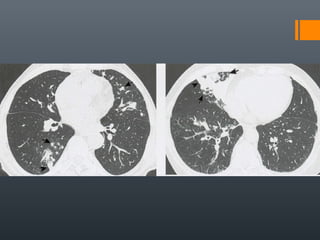

O documento discute vários conceitos radiológicos incluindo consolidação, atelectasia, nódulos, pseudocavidades e padrões intersticiais, fornecendo definições, sinais e diagnósticos diferenciais para cada tópico. Ele também discute a redução da atenuação pulmonar e fornece um link para mais informações.